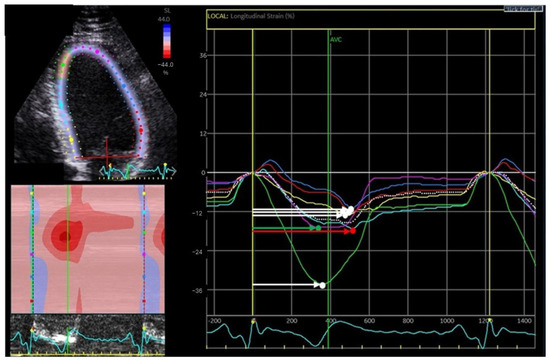

Impact of Acute Lymphoblastic Leukemia Treatment on Left Ventricular Function Assessed in 2D and 3D Speckle Tracing Echocardiography—Preliminary Results

by Julia Haponiuk-Skwarlińska, Halszka Kamińska, Katarzyna Albrecht, Paweł Łaguna and Bożena Werner

J. Clin. Med. 2025, 14(24), 8682; https://doi.org/10.3390/jcm14248682 - 8 Dec 2025

Background/Objectives: Acute lymphoblastic leukemia (ALL) is the most common childhood malignancy with promising survival. ALL treatment involves the use of cardiotoxic anthracyclines. The data for children on new methods of echocardiographic detection of early-onset anthracycline-related left ventricle dysfunction is lacking. Methods: [...] Read more.

Background/Objectives: Acute lymphoblastic leukemia (ALL) is the most common childhood malignancy with promising survival. ALL treatment involves the use of cardiotoxic anthracyclines. The data for children on new methods of echocardiographic detection of early-onset anthracycline-related left ventricle dysfunction is lacking. Methods: Consecutive children with ALL were prospectively enrolled. The echocardiography was performed after ALL diagnosis and before initiation of anthracyclines (first assessment) and after induction and intensification therapy completion (second assessment). The left ventricle echocardiographic assessment involved conventional two-dimensional (2D) echocardiography, 2D speckle tracing, and three-dimensional (3D) echocardiography with offline analysis for 3D speckle tracing. Results: The preliminary group of 32 children presented with mean time between the first and second assessment of 7.3 ± 1.5 months (min.5.3–max.11.4). All children were treated by the same treatment protocol and received doxorubicin and daunorubicin. The mean cumulative equivalent anthracycline dose was 165.6 ± 54.0 mg/m2. Statistically significant differences between the first and the second echocardiography were observed in LV-GLS-2D −24.6 ± 3.3% vs. −21.0 ± 3.3%; p < 0.001, LVEF-3D 59.7 ± 7.3% vs. 55.1 ± 3.0%; p = 0.010, LV-GLS-3D −23.3 ± 5.3% vs. −20.4 ± 2.8%; p = 0.031 and LV-GCS-3D −26.3 ± 5.9% vs. −21.9 ± 3.2%; p = 0.017. The differences in LVEF-2D and LV-GRS-3D were not statistically significant. The decrease of >15% from the first assessment was observed in 9 (28%) in LV-GLS-2D, 8 (25%) in LV-GLS-3D, 11 (34%) in LV-GCS-3D and only in 4 (13%) patients in LV-GRS-3D. Conclusions: Two-dimensional and three-dimensional speckle tracing and 3D-LVEF may be sensitive indicators of subclinical left ventricular function impairment in children treated for ALL with anthracyclines. However, this is a preliminary analysis of the planned cohort; our results should be interpreted with caution. Full article

Show Figures

Figure 1